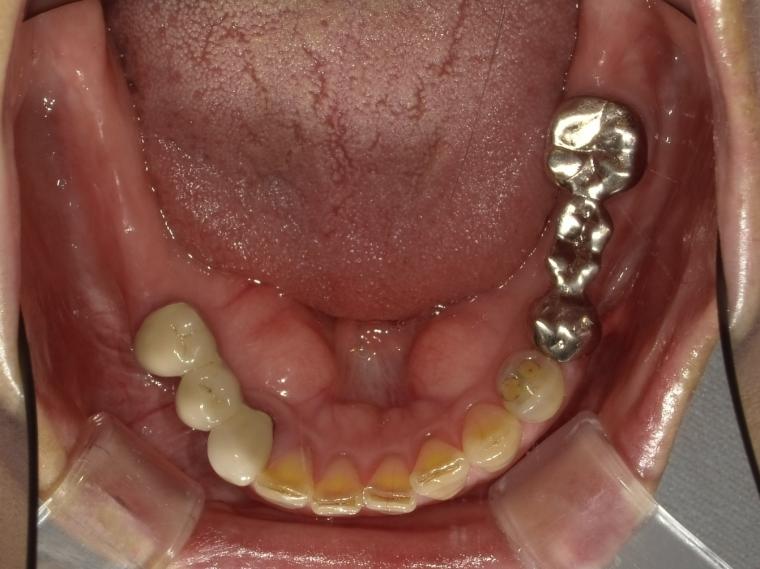

BEFORE

74歳女性

/上下3本/インプラント埋込手術

【治療内容】

欠損補綴のご相談でご来院された患者さんです。

義歯とインプラントのメリット・デメリットやリスクなど、それぞれ考えた上でインプラント治療を選択されました。